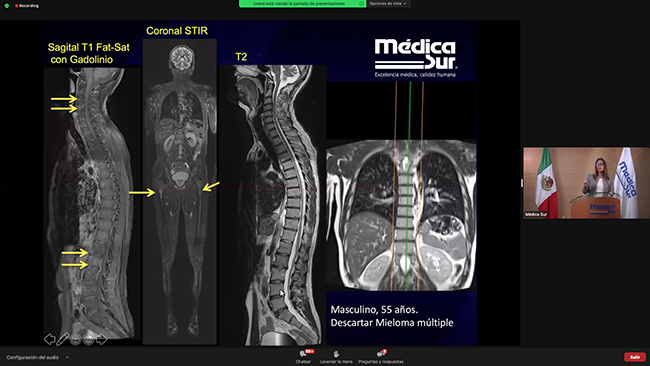

15:30 - 16:00 · Resonancia magnética body, indicaciones y técnica

Dr. Digna Pachuca González